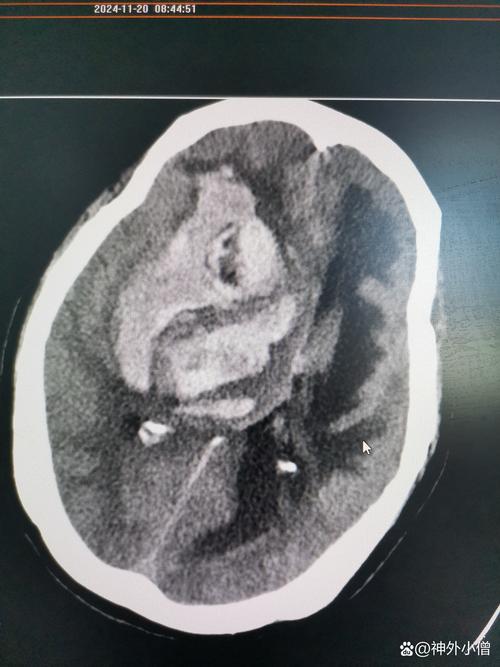

(图片来源网络,侵删)